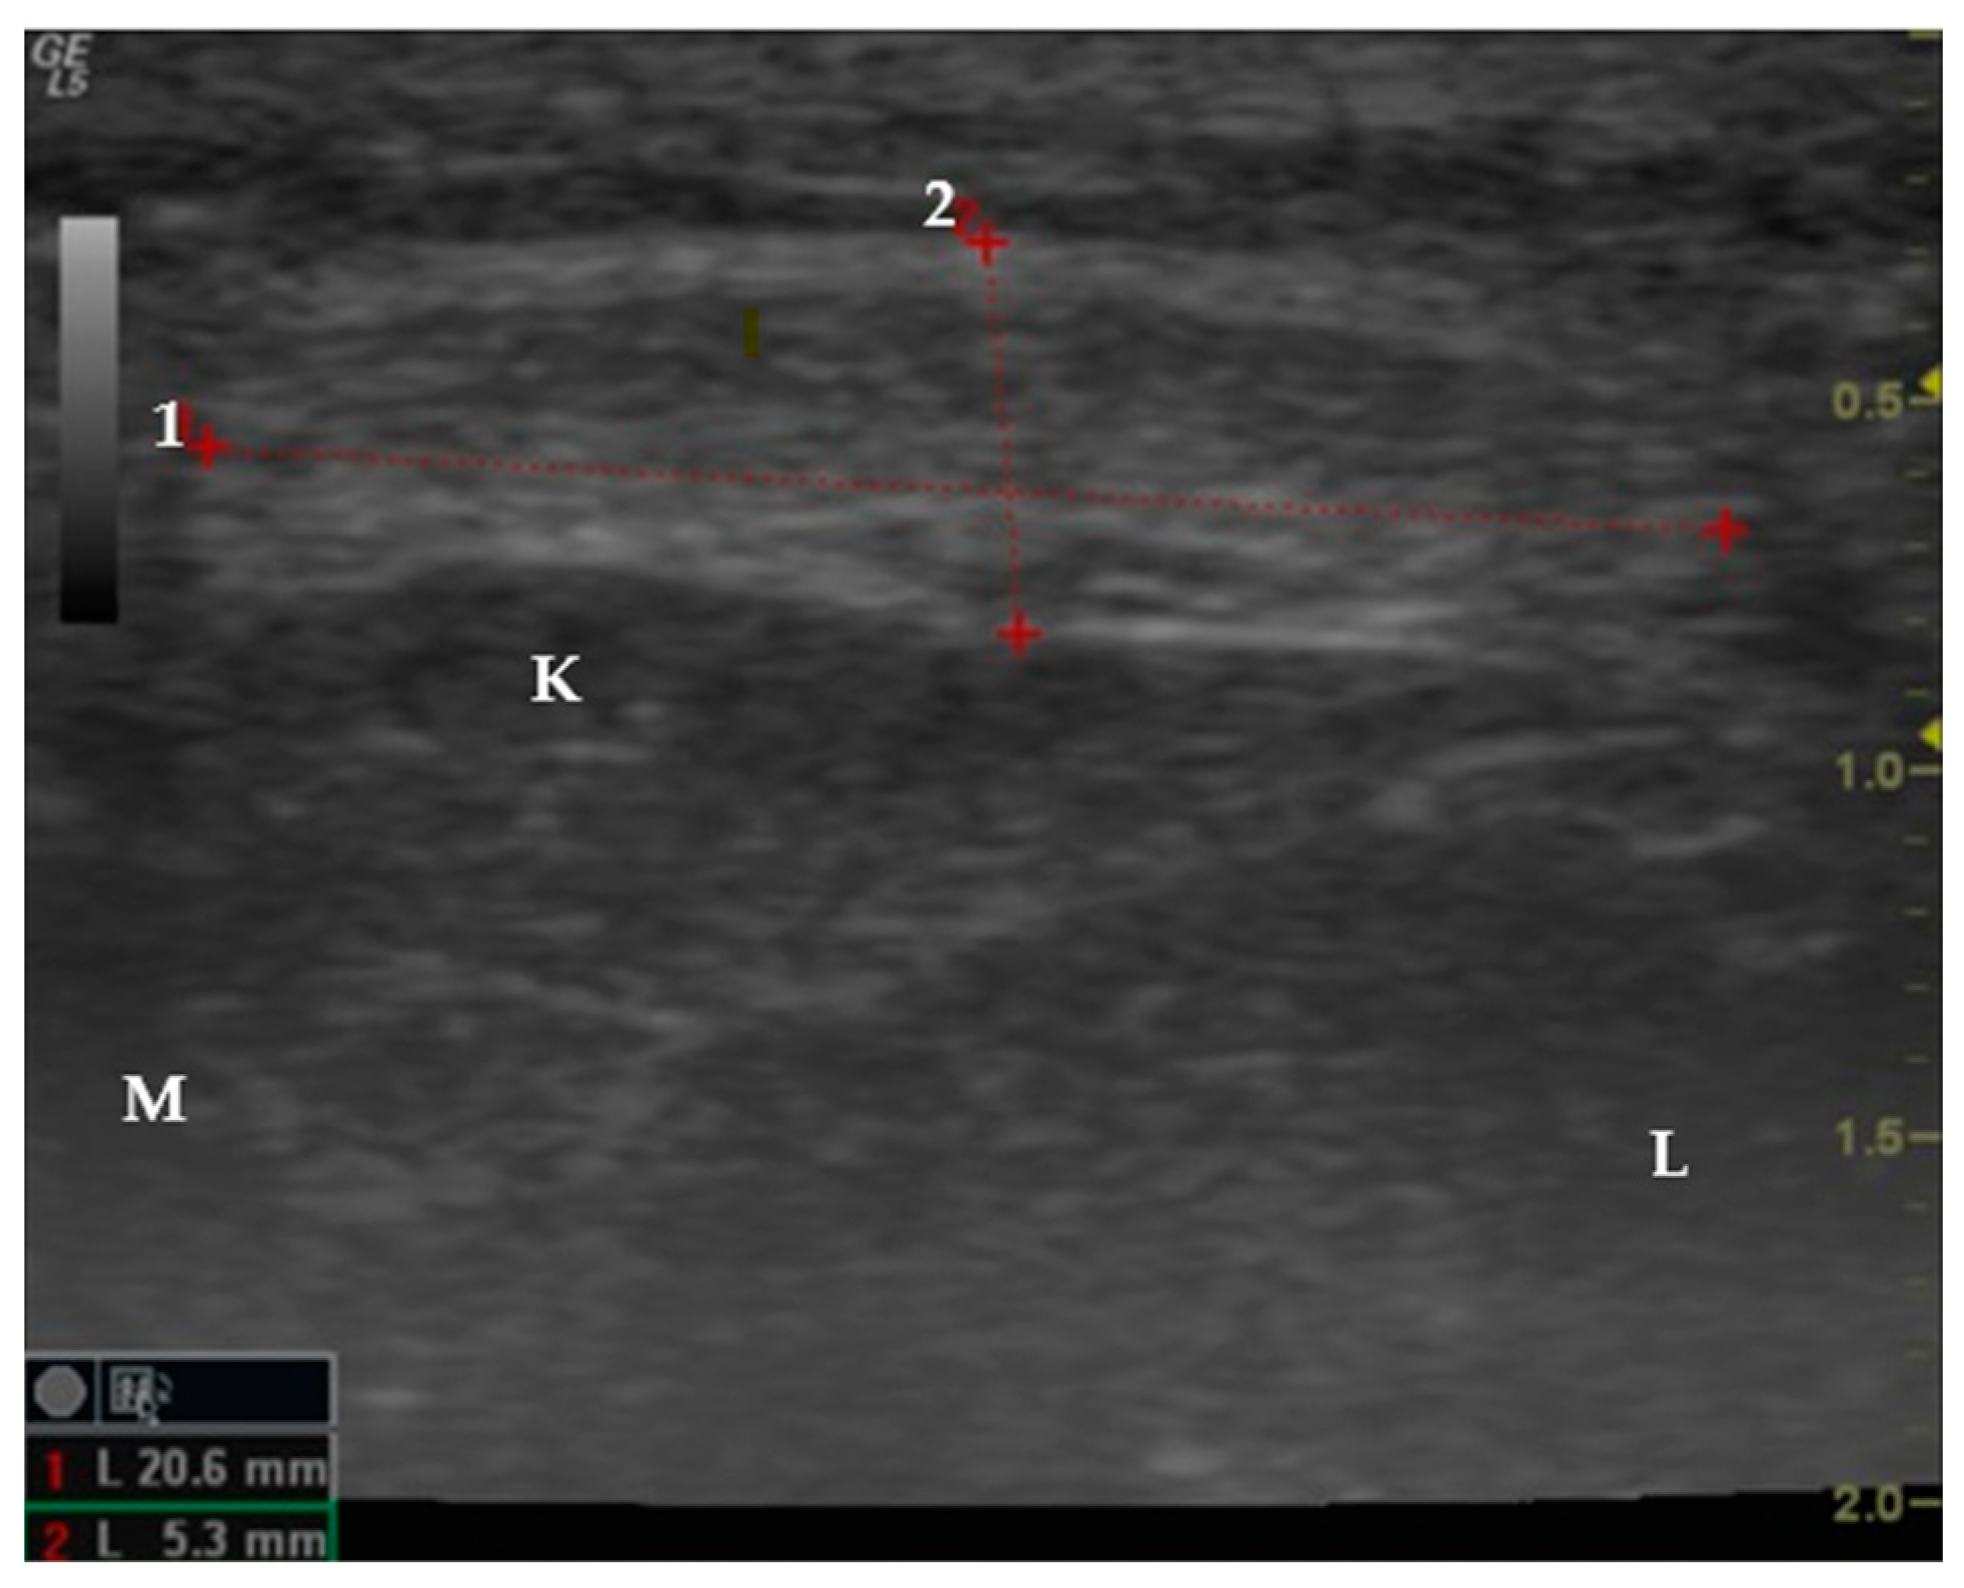

2.3. Data Collection